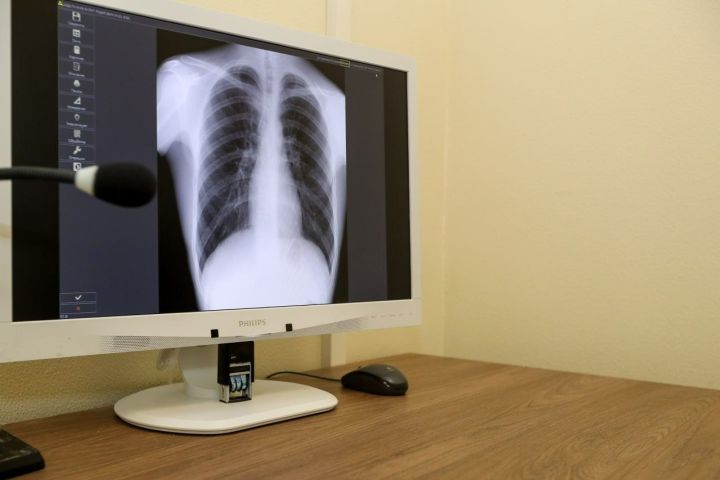

Профилактика рака легких: современный взгляд и перспективы

Отказ от курения, защита от вредных факторов окружающей среды, здоровый образ жизни и регулярные медицинские проверки - ваше главное оружие в борьбе с этим страшным заболеванием

Рак легких остается одним из самых опасных видов онкологических заболеваний. По всему миру он занимает лидирующие позиции по частоте смертности среди рака. Однако ученые и врачи неустанно работают над тем, чтобы помочь людям избежать этого заболевания. В основе успешной борьбы с раком легких лежит профилактика — комплекс мер, направленных на предупреждение развития болезни. О том, как уберечься от рака легких, о новшествах и перспективах в этой области рассказали специалисты Республиканского центра общественного здоровья и медицинской профилактики — заместитель главного врача Рушана Валиева и врач Никита Чумарев.

Для людей из групп риска (курильщики старше 50 лет, работники вредных производств) врачи рекомендуют прохождение скрининга — специального обследования, чаще всего с помощью низкодозной компьютерной томографии (КТ). Это позволяет выявить рак на ранней стадии, когда лечение наиболее эффективно.